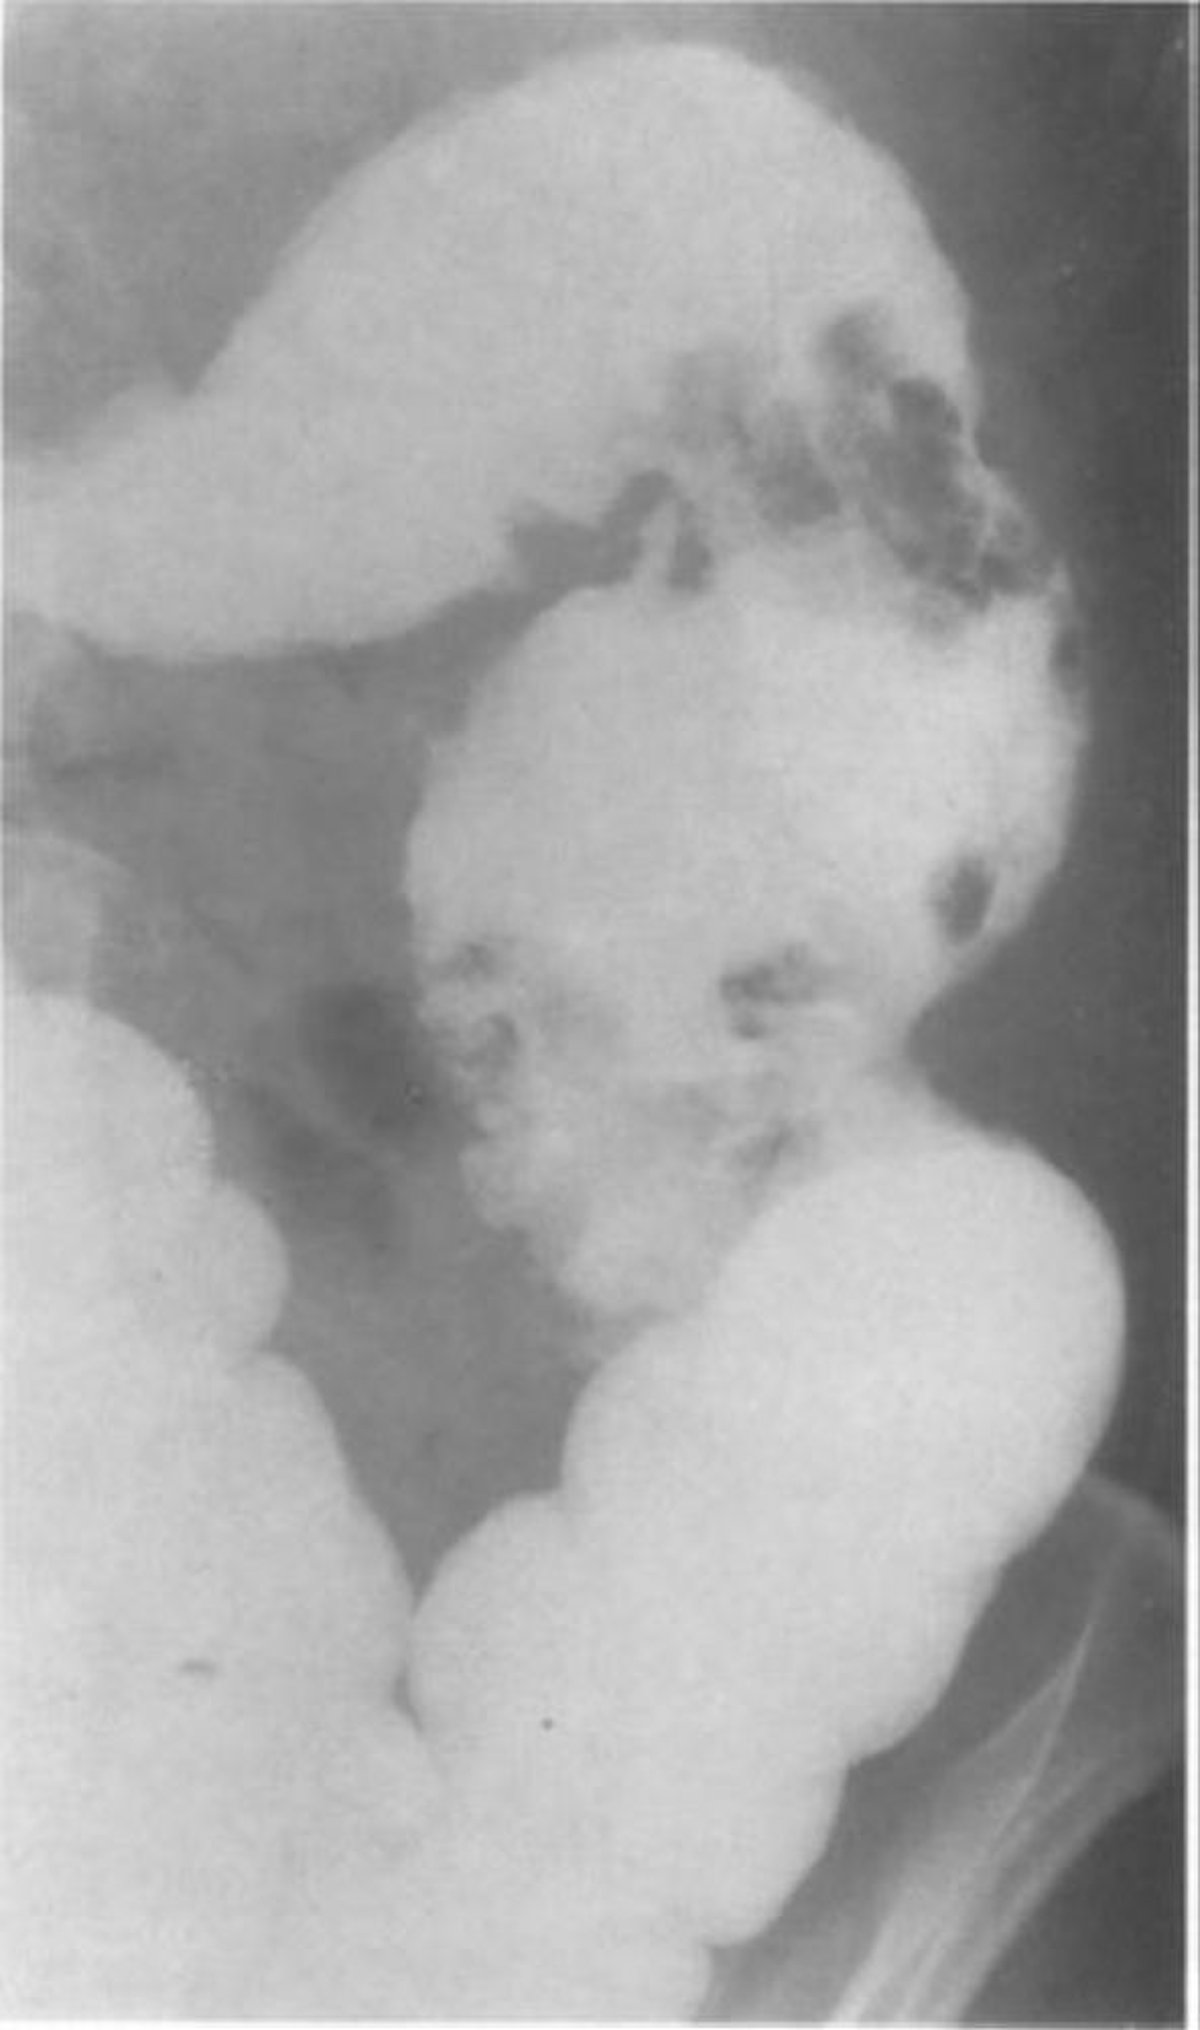

Thuốc xổ bari cho thấy giả polyp niêm mạc

Hình ảnh một bệnh nhân bị viêm đại tràng u hạt cho thấy 2 cụm giả polyp lớn ở đại tràng xuống.